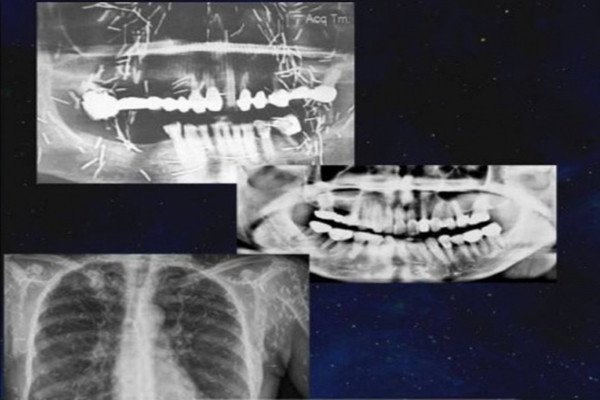

| Khi kiểm tra kết quả chụp CT, máu và chụp X-quang của bệnh nhân, bác sĩ phát hiện bệnh nhân này cấy rất nhiều kim bùa vào mắt, mặt, cổ và ngực. |